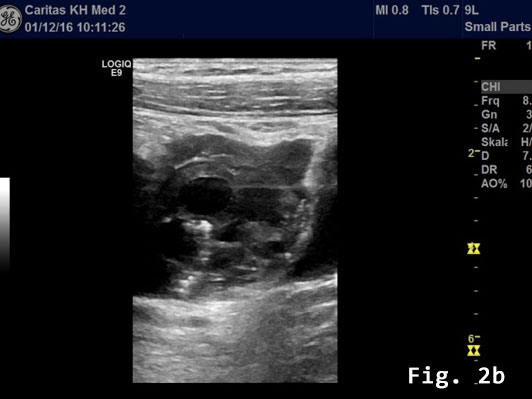

Transabdominal B-mode ultrasound (BMUS) confirmed a 40 mm sized heterogeneous hy-poechoic lesion infiltrating the sigmoid colon [Figure 2].

Endorectal endoscopic ultrasound of the sigmoid colon revealed transmural extension of the mass and confirmed the transcutaneous finding. The lesion was well vascularized [Figure 2].